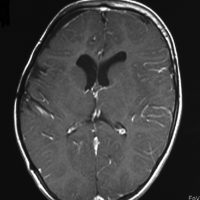

teratomaのparadoxical response

neurohypophyseal mixed germ cell tumorの若年成人男子例です。発症時のMRIでは大部分が増強されますが,腫瘍の右前方に脂肪組織を示す小さな信号域を認めます(上段左の単純MRI,上段右の増強MRI)。経蝶形骨洞生検術でmature teratomaとgerminomaの所見が得られました。ICE化学療法により増強される部分の腫瘍は消失しましたが,逆に下段左の単純MRIと下段中央のCTで認められる脂肪組織を含む部分が顕著に増大しました。この腫瘍は後に亜全摘出しました(下段右)が,病理所見は類皮腫でした。teratomaにおいてはこのような奇異な治療反応性 paradoxical response がみられることがあります。